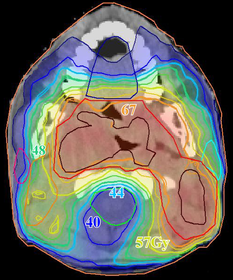

B

eam

A

ngle

O

ptimisation (

BAO

) in

I

ntensity

M

odulated

R

adiation

T

herapy (

IMRT

)